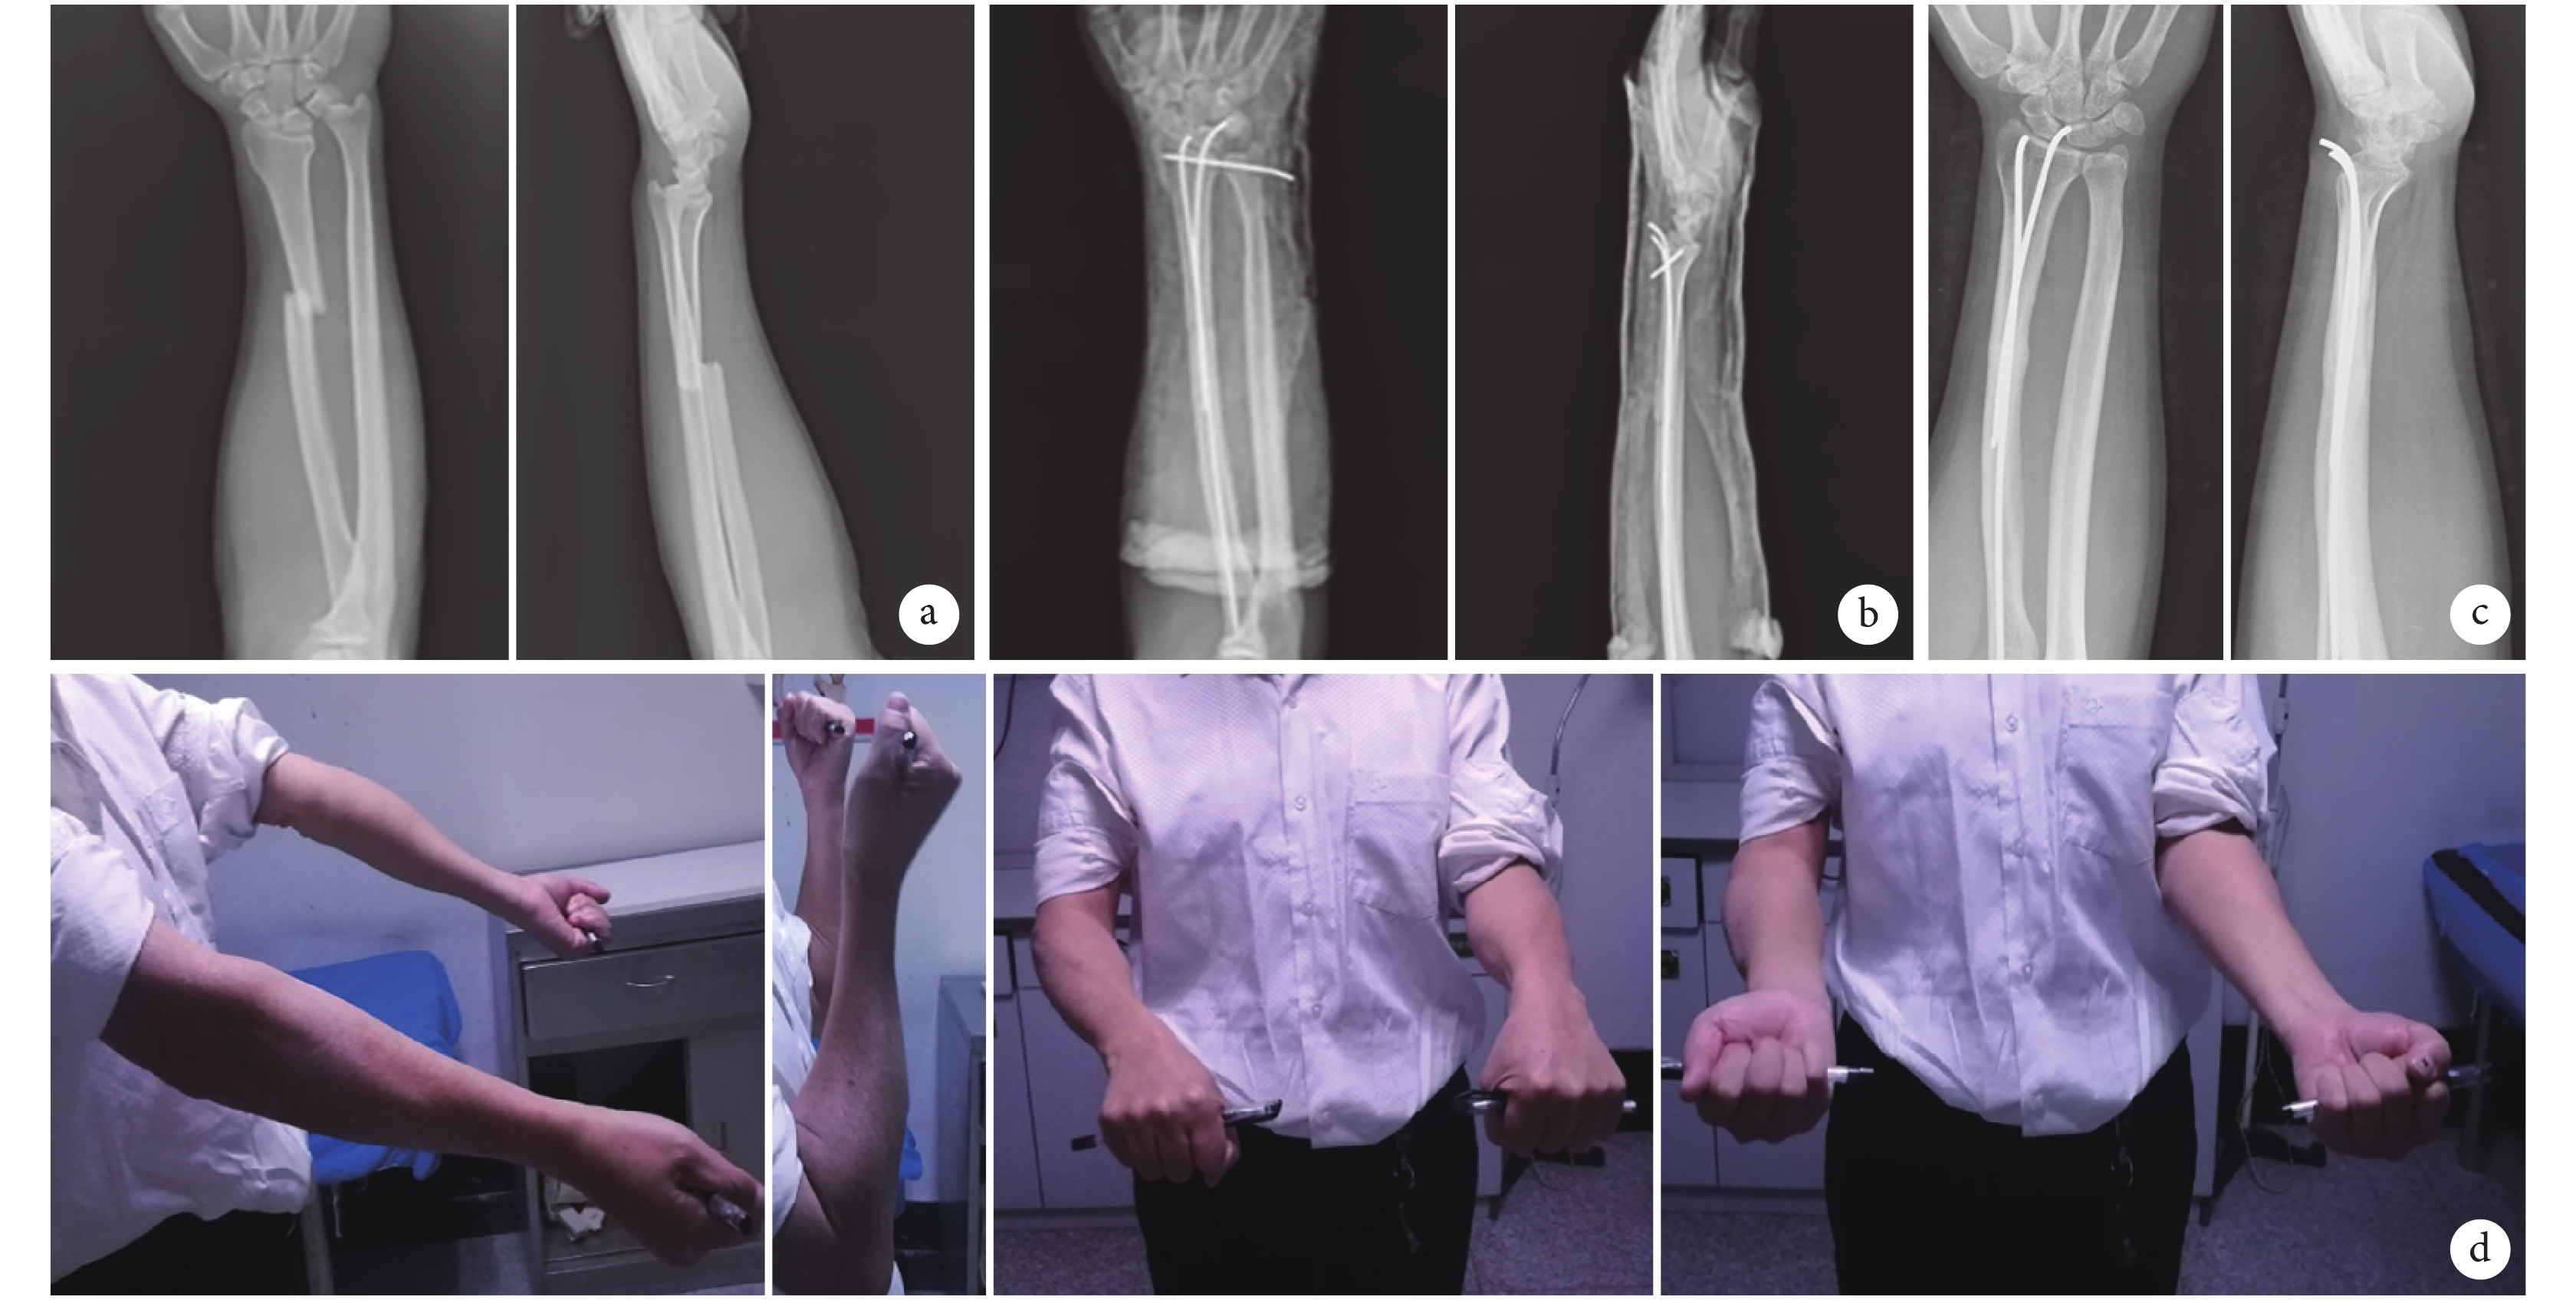

a. 術前正側位 X 線片;b. 術后即刻正側位 X 線片;c. 術后 4 個月正側位 X 線片示骨折斷端已骨性愈合,斷端可見大量骨痂形成;d. 術后 12 個月患肢屈伸旋轉功能完全恢復

Figure2. A 42-year-old male patient with Galeazzi fracture of the left forearm caused by fall from height in minimally invasive groupa. Anteroposterior and lateral X-ray films before operation; b. Anteroposterior and lateral X-ray films at 1 day after operation; c. Anteroposterior and lateral X-ray films at 4 months after operation, there were a large number of callus in the fracture and the fracture had healed; d. Pronation, supination, flexion, and straighten function of wrist joint at 12 months after operation